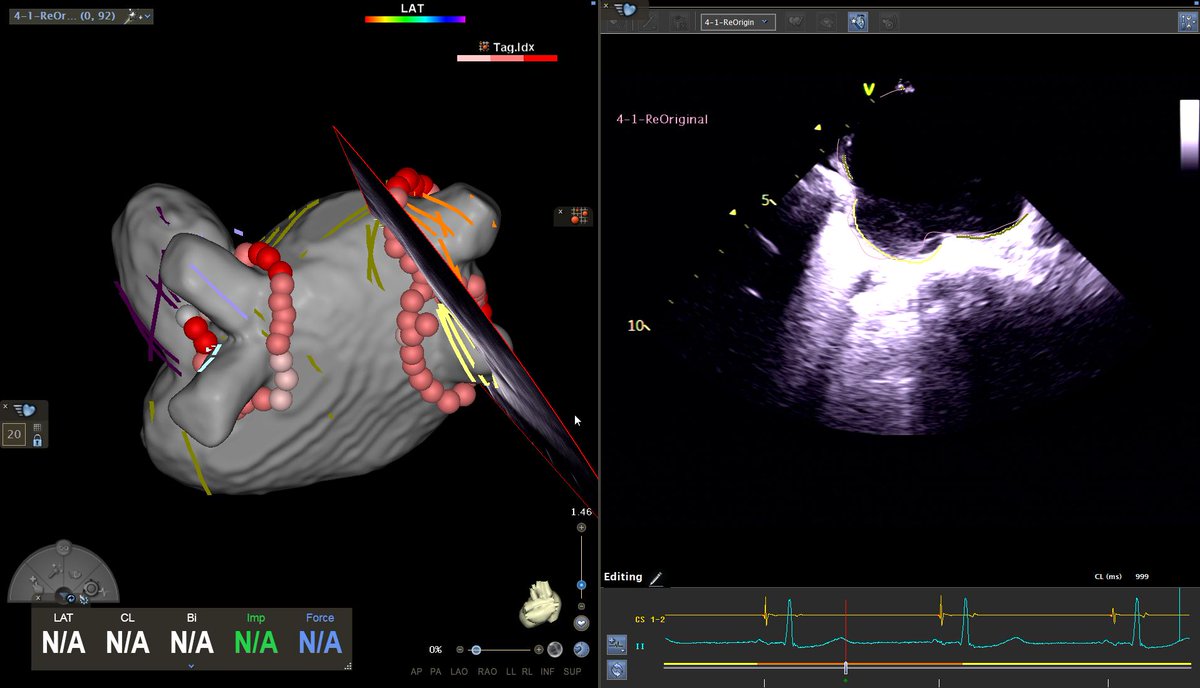

Interesting focal AT in our first Live Course as a Biosense Center of Excellence, with 4 seconds of RF to termination. As usual, ICE making our life easier. Looking forward to our next session!

@BiosenseWebster @EpCardiac @JustoJuli1 @SimonJewell10 @AlexBarbour6